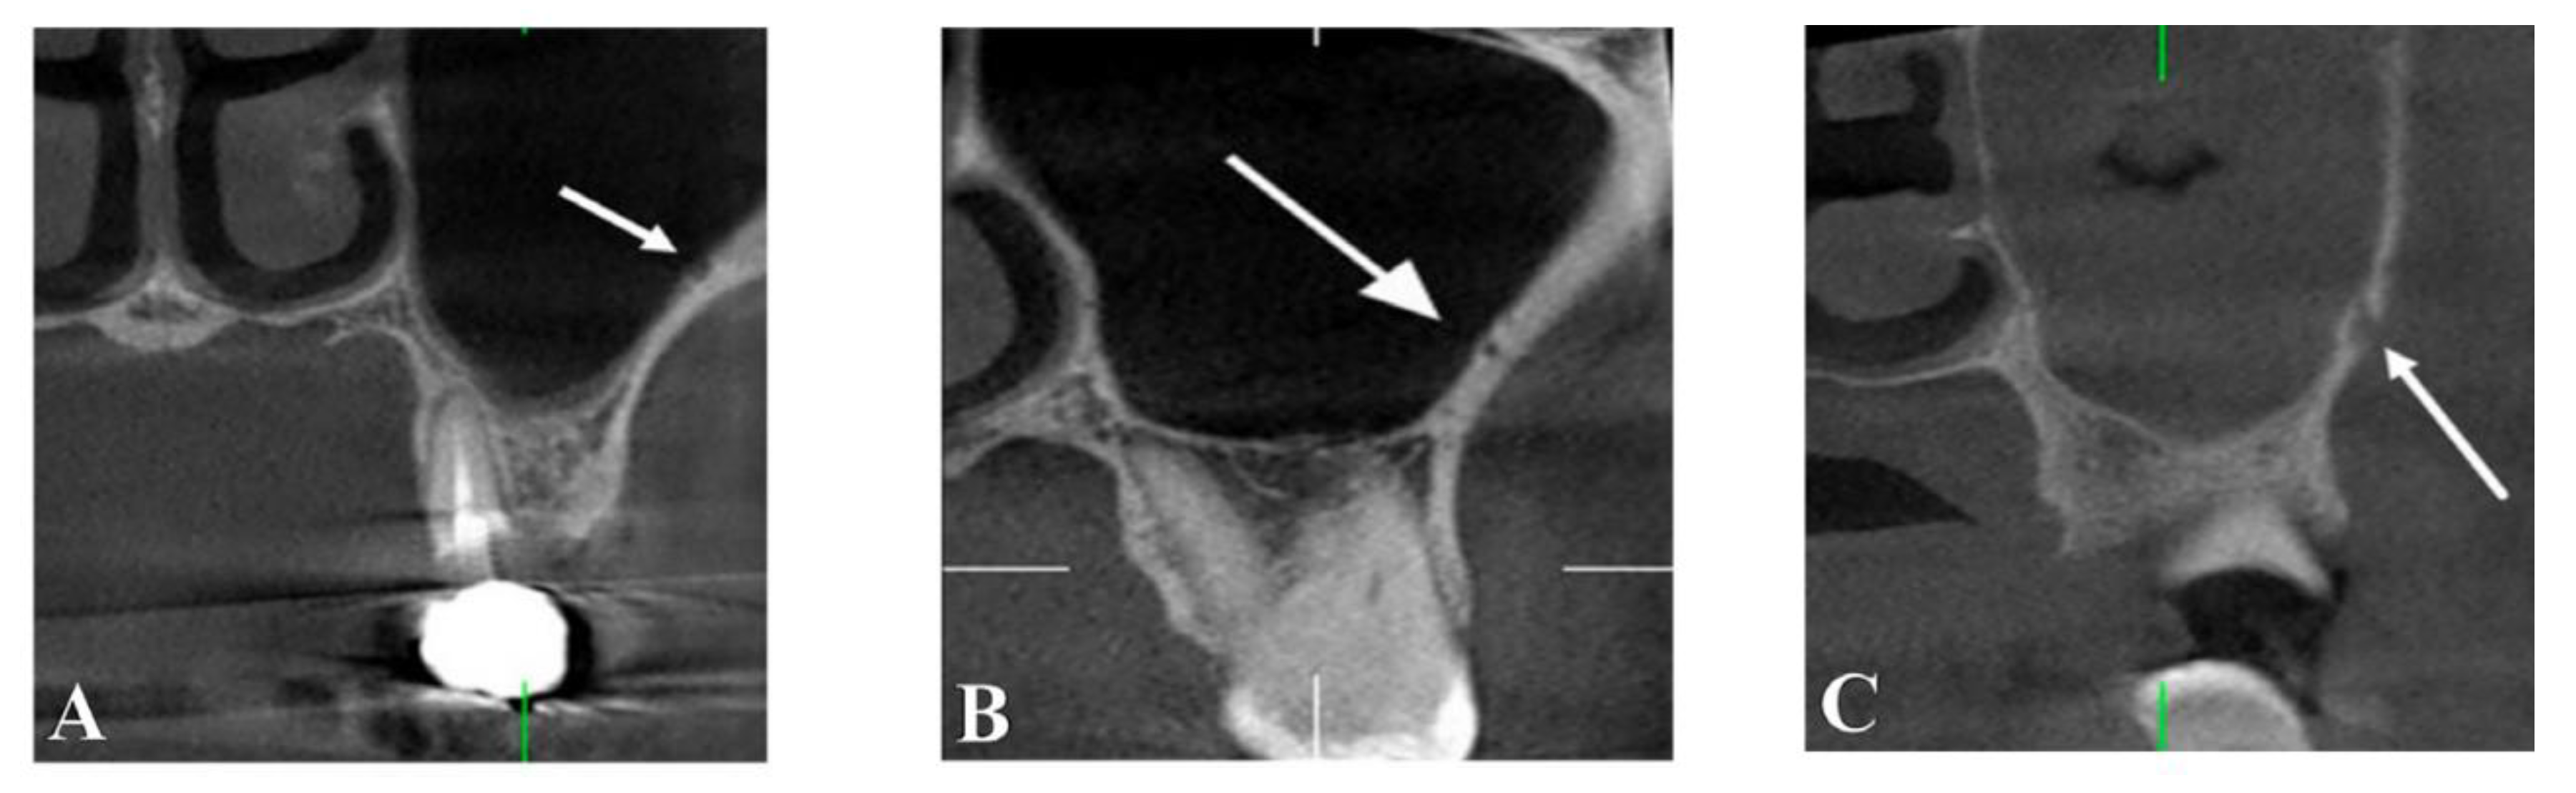

Posterior superior alveolar artery

Mentonian Hole